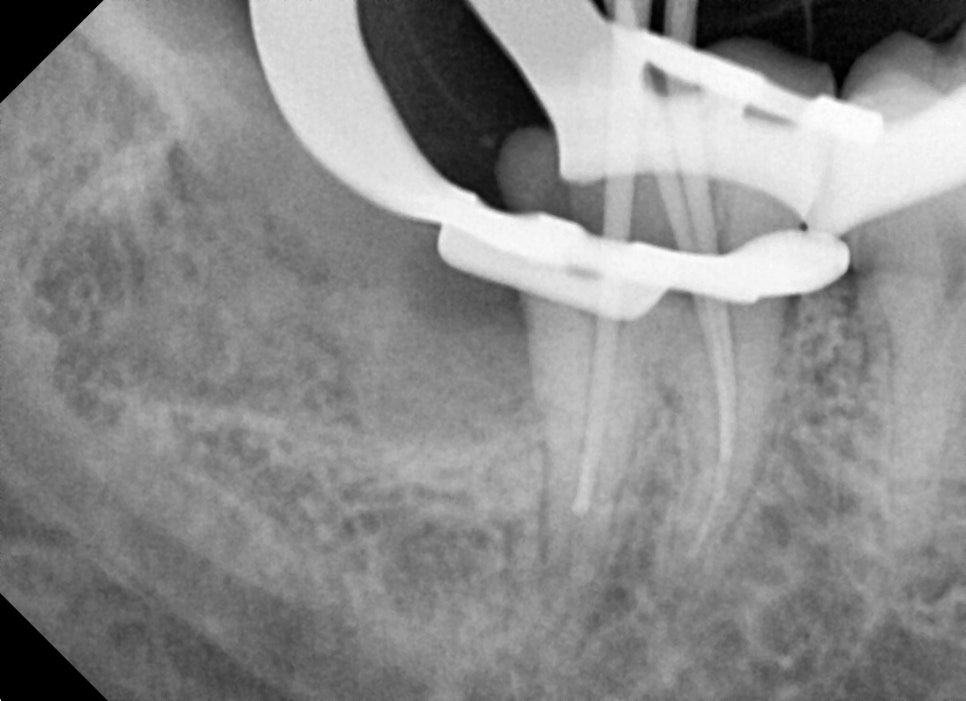

조금이라도 시야 확보를 위해 신경치료 중간에 사랑니 발치를 실시했습니다.

치아 뿌리가 조금 휘어있네요.

뿌리끝 길이를 사진으로 확인하며 마무리를 해줍니다.

사랑니 발치는 신경치료 마무리 전에 약간의 잇몸 절개와 치조골 삭제를 통해 발치를 했습니다.